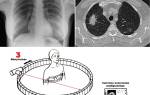

Компьютерная томография – это высокотехнологичный метод, позволяющий получать послойные изображения внутренних органов и тканей. Основной принцип работы заключается в использовании рентгеновских лучей, которые проходят через тело под различными углами. Датчики томографа фиксируют ослабление этих лучей, когда они проходят через разные ткани организма. Затем собранные данные обрабатываются с помощью специализированного программного обеспечения, что позволяет создать трехмерную модель исследуемой области.

Современные компьютерные томографы обладают впечатляющей скоростью сканирования – до 320 срезов в секунду. Это дает возможность получать максимально четкие изображения даже движущихся объектов, таких как сердце или легкие. Толщина среза может варьироваться от 0,5 до 10 мм, в зависимости от типа исследования и поставленных задач. Чем меньше толщина среза, тем более детализированным будет изображение.

Компьютерная томография (КТ) использует рентгеновские лучи для создания детализированных изображений внутренних органов и тканей. Во время процедуры рентгеновская трубка вращается вокруг пациента, делая множество снимков с разных углов. Эти изображения затем обрабатываются компьютером, который создает поперечные срезы тела, позволяя врачам видеть структуру органов в трехмерном формате.